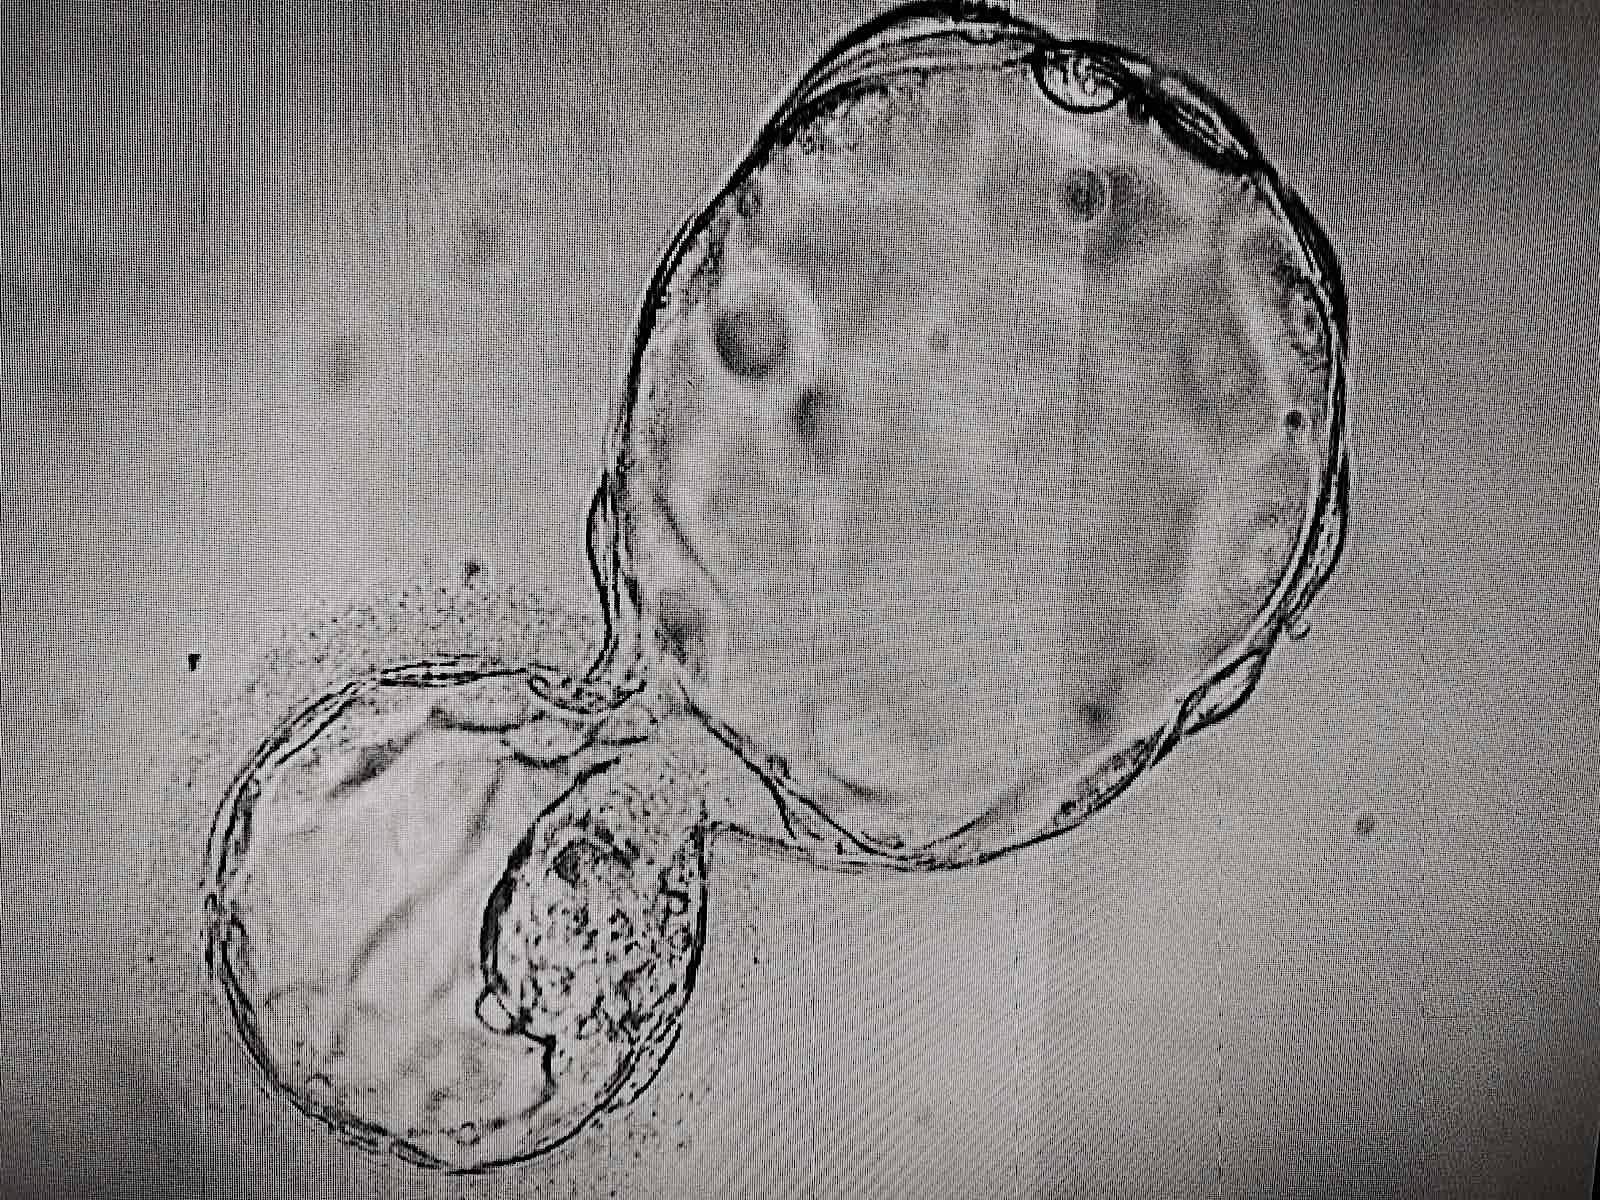

High quality blastocysts, with the euploid set of chromosomes, 46,ХХ

High quality blastocysts, with the aneuploid set of chromosomes, 49,Х,+3,+5,+18,+21

A high-quality blastocyst has a multicellular trophectoderm, from which the placenta is subsequently formed, and a compact intracellular mass, from which the embryo is formed.

Embryos with multiple chromosomal abnormalities may stop in development, have fragmentation of the cytoplasm, uneven blastomeres, small-cell trophectoderm, non-compact intracellular mass.